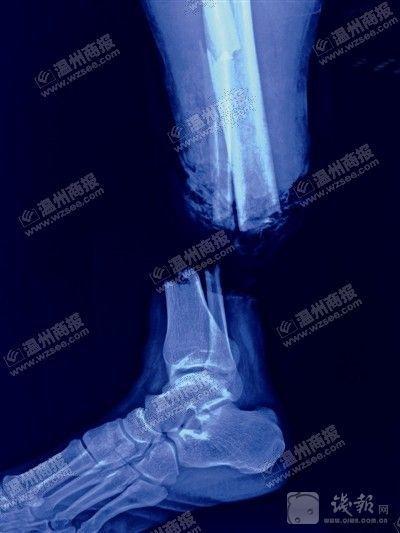

X光显示鲍成远右小腿完全被勒断。医院供图金鱼翻拍

刘斌告诉记者,在缆绳巨大作用力下,鲍成远右小腿伤口周围皮肤被挤压变形,近端皮肤缺损,胫骨粉碎性骨折,腓骨多段骨折。

手术过程中,他们对鲍成远伤口处一些挫烂后无生机、无活力的软组织进行剪除。然后,通过锁钉螺钉对骨折部位进行固定,接着,从身体其他部位移植肌腱、血管等,在显微镜下,对右小腿缺损的肌腱、血管等处进行缝接。经过10余小时手术,鲍成远的断腿终于成功接回。